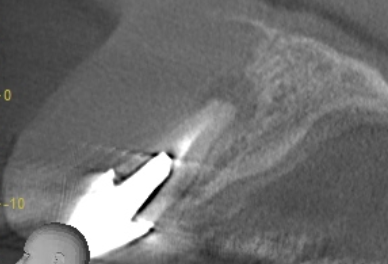

レントゲンで確認したこと|根の先に膿がたまり、骨が吸収されていました

レントゲンでは、歯の根の先に膿がたまっており、周囲の骨が大きく吸収されている状態が確認されました。

感染した歯をそのまま残すと、周囲の健康な歯や骨にも悪影響を及ぼすおそれがあります。

そのため、感染源となっている歯を抜歯し、根の先にたまった膿の袋を取り除いたうえで、将来的なインプラント治療に向けて骨と歯ぐきの状態を整える方針としました。